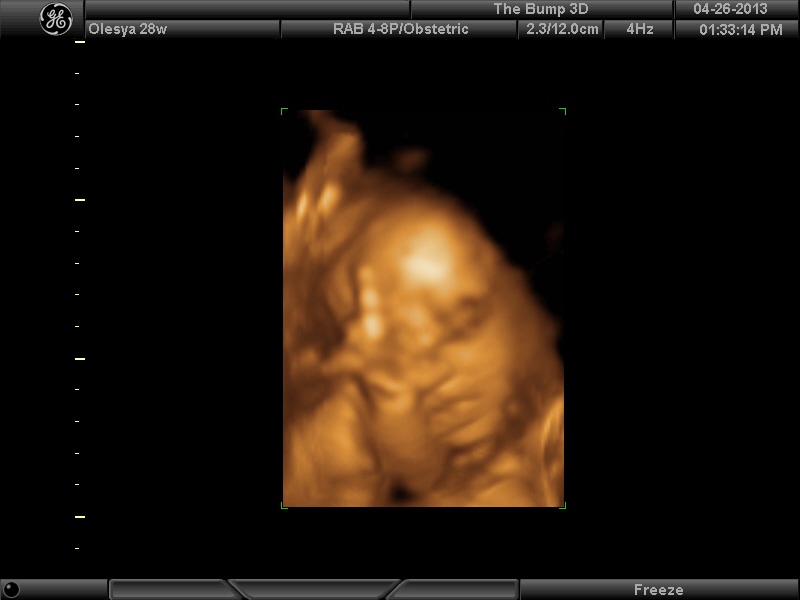

| Ксюнь, а мы вообще не поняли. Она на всех фотках разная, да еще размытость такая. Пуповина то на носу болталась, то руками-ногами закрывалась. Главное что четкости нет совсем.  Лоб у мужа тоже большой, а носы и губы зачастую на 3Д-4Д выходят разамазанно-пухло-приплюснутыми    Поставлю для наглядности фотку моей средней-Джианки с 3Д УЗИ, там видно черты намного лучше и она на себя ту похожа сейчас, хотя родилась мне совсем на фото УЗИ не казалась похожей.

| Вложения: |

|  KENZEL,OLESYA_3.JPG [ 56.84 КБ | Просмотров: 1163 ]

| Катюш, какой прикольный бутузик  ! Олесь, после фотки средней - точно прям похожи!